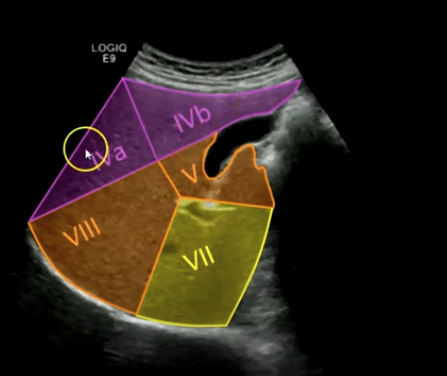

Cantlie's Line:

An imaginary line that extends from the gallbladder fossa to the inferior vena cava (IVC). It contains the gallbladder and middle hepatic vein, separating segments four, five, and eight. This line is crucial for surgical planning.

Middle finger: Segments four a and four b.

Superior segments of the liver: Segment two, segment four a, and segment eight.

Superior segment of the right lobe (transverse): Hepatic veins, segments four a, eight, and seven.

Middle hepatic vein separates four a from eight.

Right hepatic vein separates eight from segment seven.